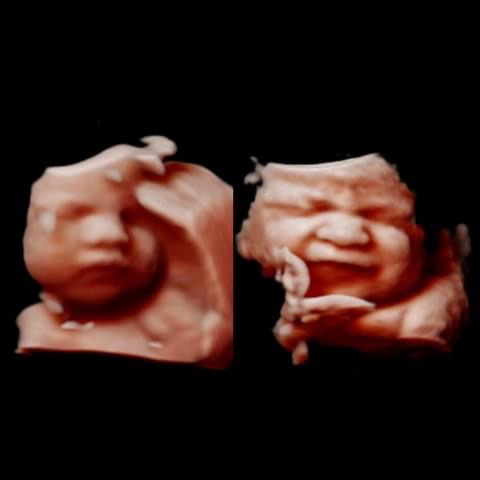

All photos are from our equipment and are of our actual clients.